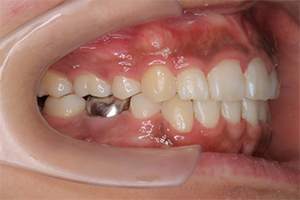

矯正治療のCASE 05

Before

After

- 主訴

- 歯並びがガタガタしていて清掃しにくい

- 治療内容

- ラビアル矯正(表側)

抜歯あり

- 治療費用

- 88万円~(税込)

- 治療期間

- 20か月

【リスク・副作用】

歯の痛み、口内炎、歯磨きがしにくいことによるむし歯や歯周病のリスク、歯根吸収や歯の変色、後戻りなどの副作用があります。